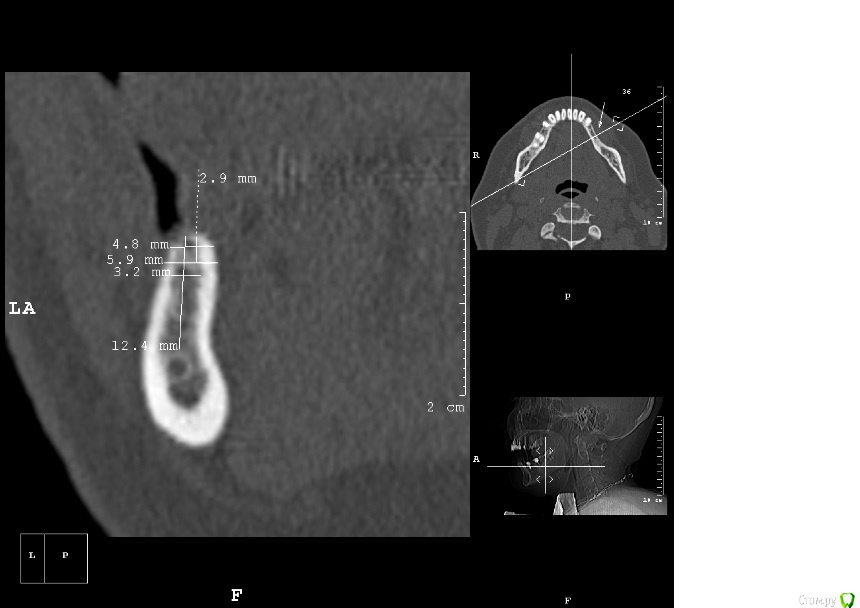

dantist_movani Опубликовано 2 мая, 2016 Поделиться Опубликовано 2 мая, 2016 Без обид, но срезы вообще ни о чем! Если есть рентгенолог или более опытный врач, сделайте новые срезы и залейте, посмотрим. Что хотите удалять, тоже не понял Ссылка на комментарий

dantist_movani Опубликовано 2 мая, 2016 Поделиться Опубликовано 2 мая, 2016 Спасибо, ответы давно уже получил, и дело не в срезах вовсе, чем вам срезы не угодили?на срезах указаны позиции 3.5,3.6,3.7,3.8? В какие позиции "3 винта" и что удалить, я просто может не понял? Ссылка на комментарий

kamranchick Опубликовано 2 мая, 2016 Автор Поделиться Опубликовано 2 мая, 2016 ну я указал 3 сегмент, 3 винта, следовательно удаление 5 го зуба, установка имплантатов в область 35 36 и 37 Ссылка на комментарий